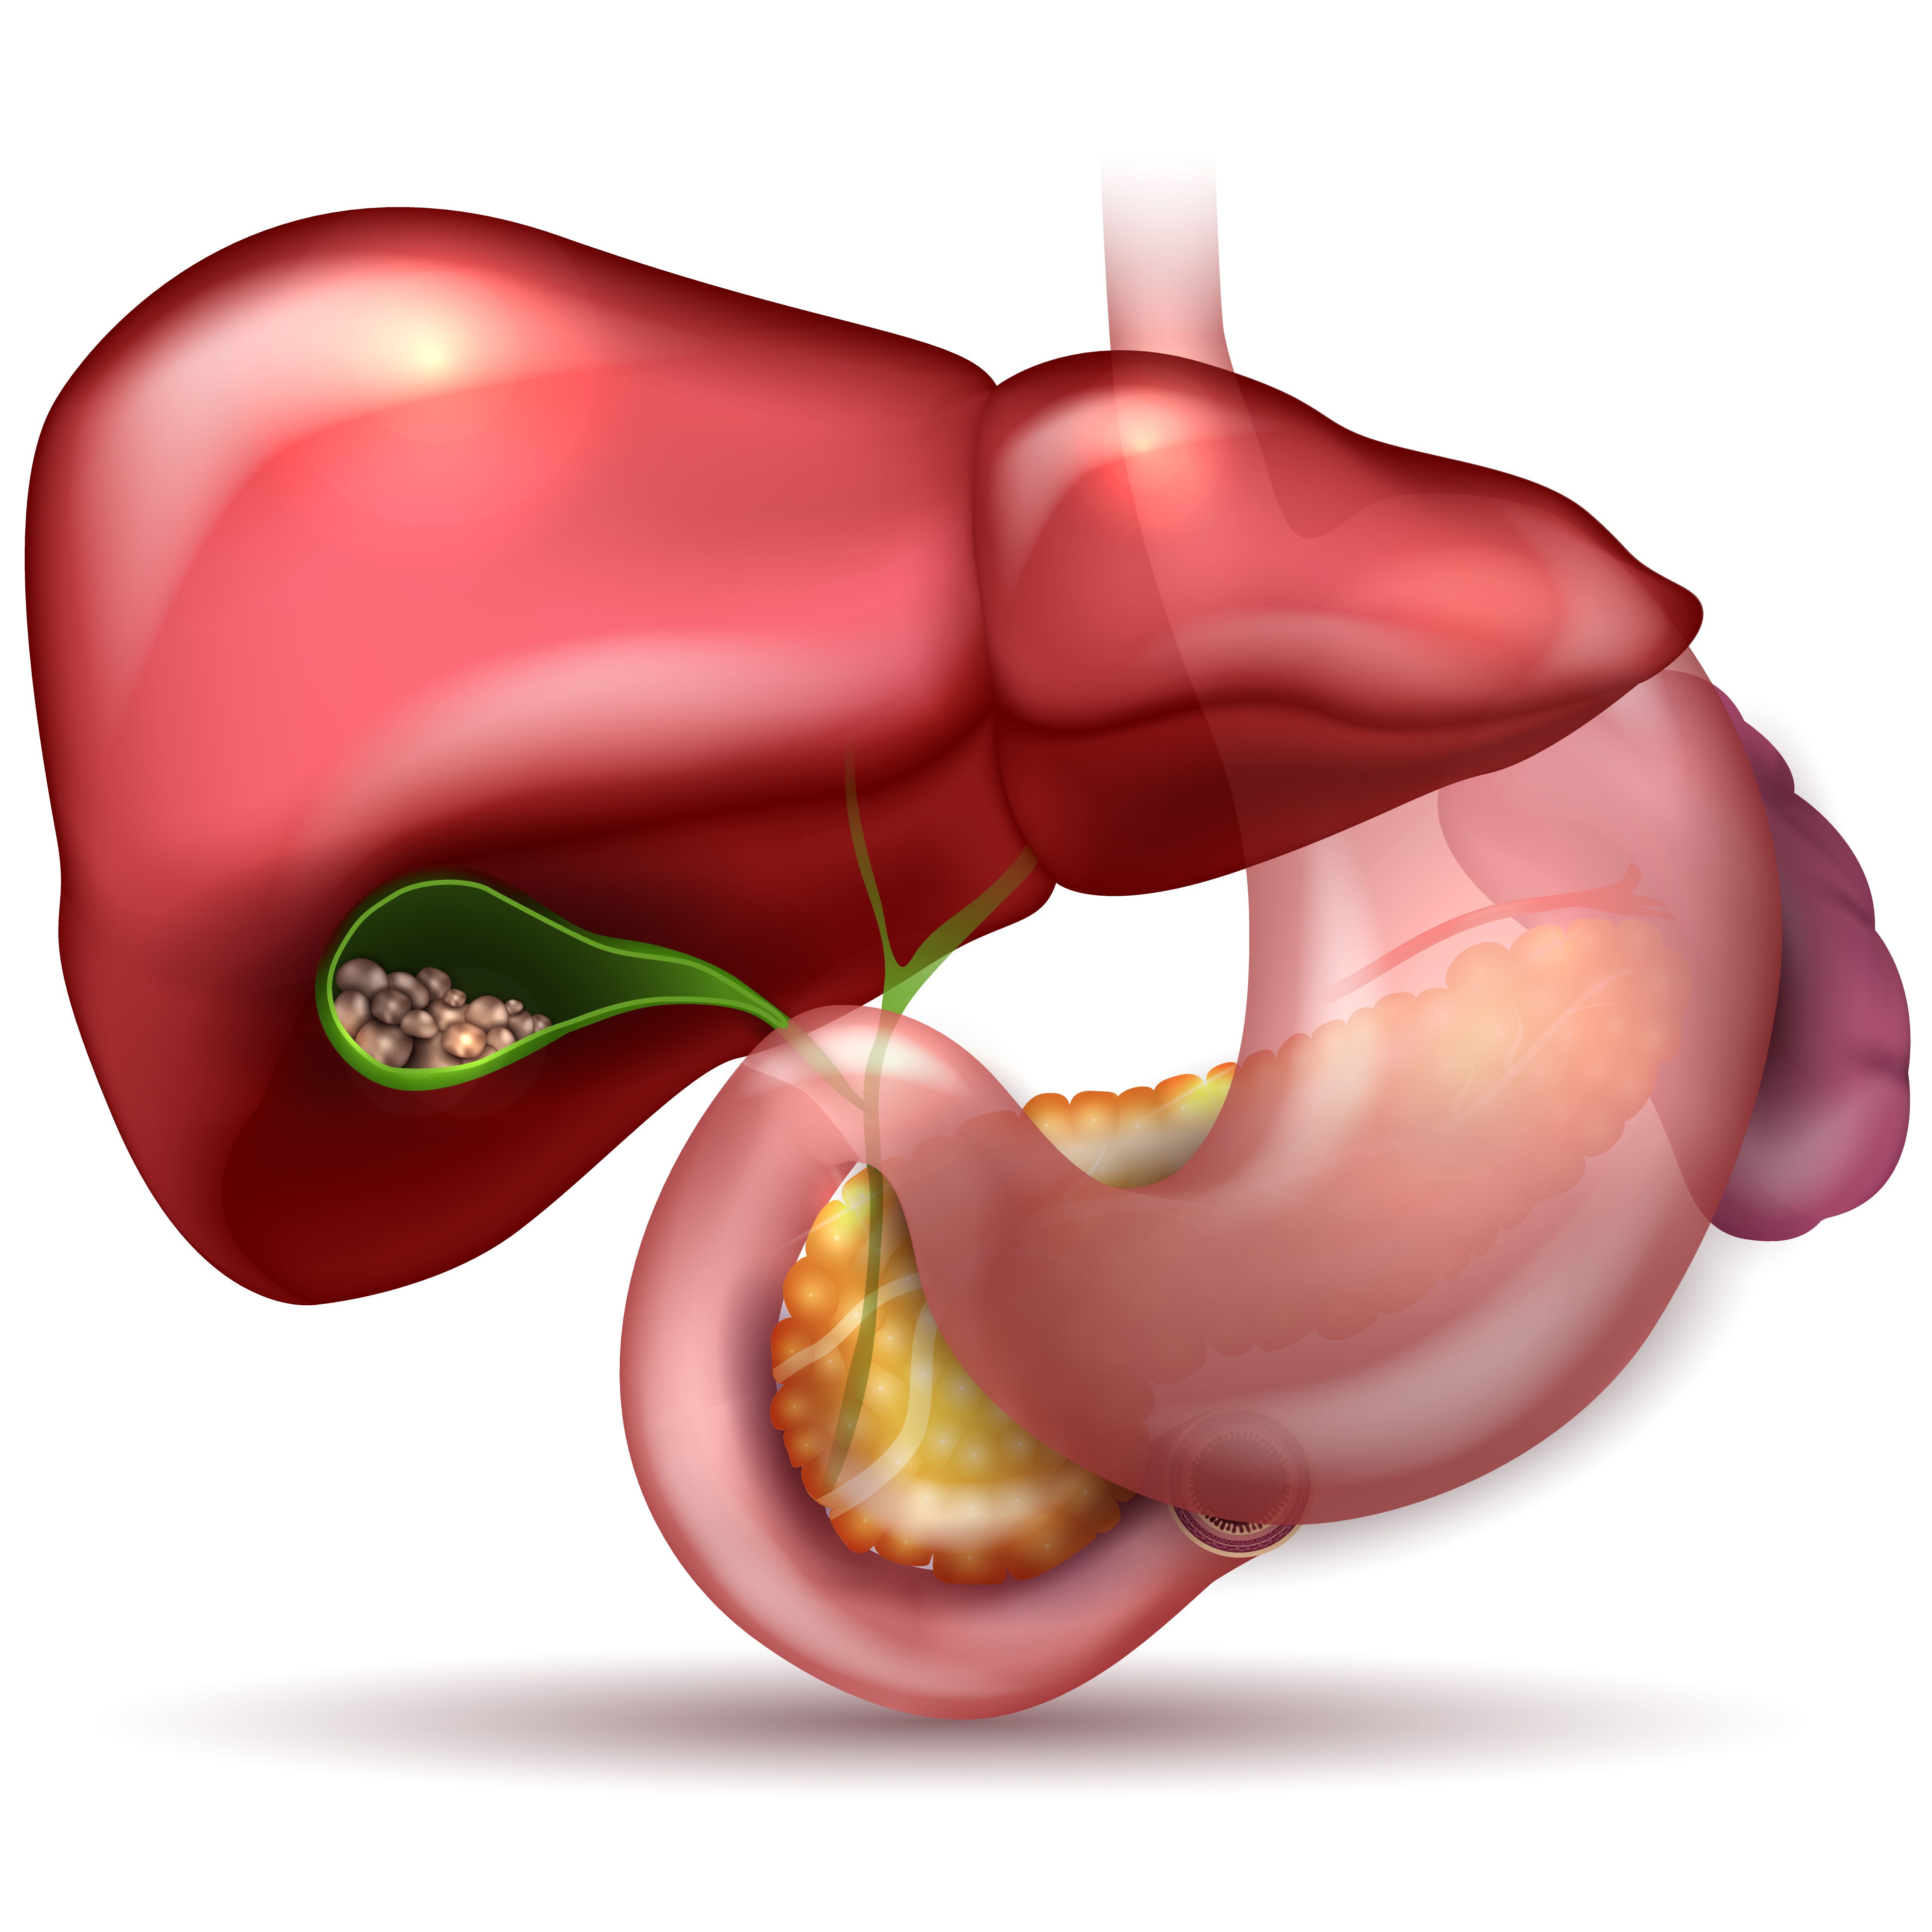

Cirugía de Vesícula

La vesícula es el órgano de nuestro cuerpo que se encarga de almacenar la bilis, un líquido producido por el hígado que ayuda a procesar la grasa de los alimentos durante la digestión. Los padecimientos de la vesícula, una vez diagnosticados, deben tratarse obligatoriamente con una operación de vesícula.

Cálculos biliares

Es la presencia de litos (piedras) en la vesícula, formados por minerales solidificados. Si estas piedras llegan a estancarse en la salida de la vesícula, pueden provocar dolores intensos y la necesidad de una operación de emergencia.